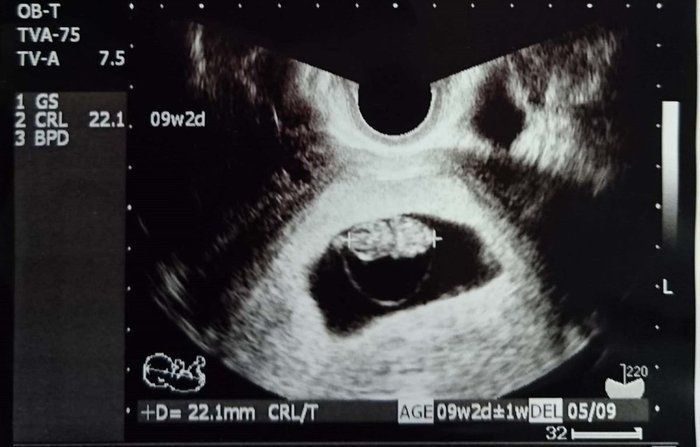

Amiさんの妊娠9週目のエコー写真

この写真から、胎嚢の中のわが子が二頭身になっていることがわかります。赤ちゃんの大きさは18.9mm。ちょうど枝豆一粒くらいの大きさです。それほど体調に変化もなく、「本当に自分のおなかに赤ちゃんがいるのか」と不思議な気持ちでした。